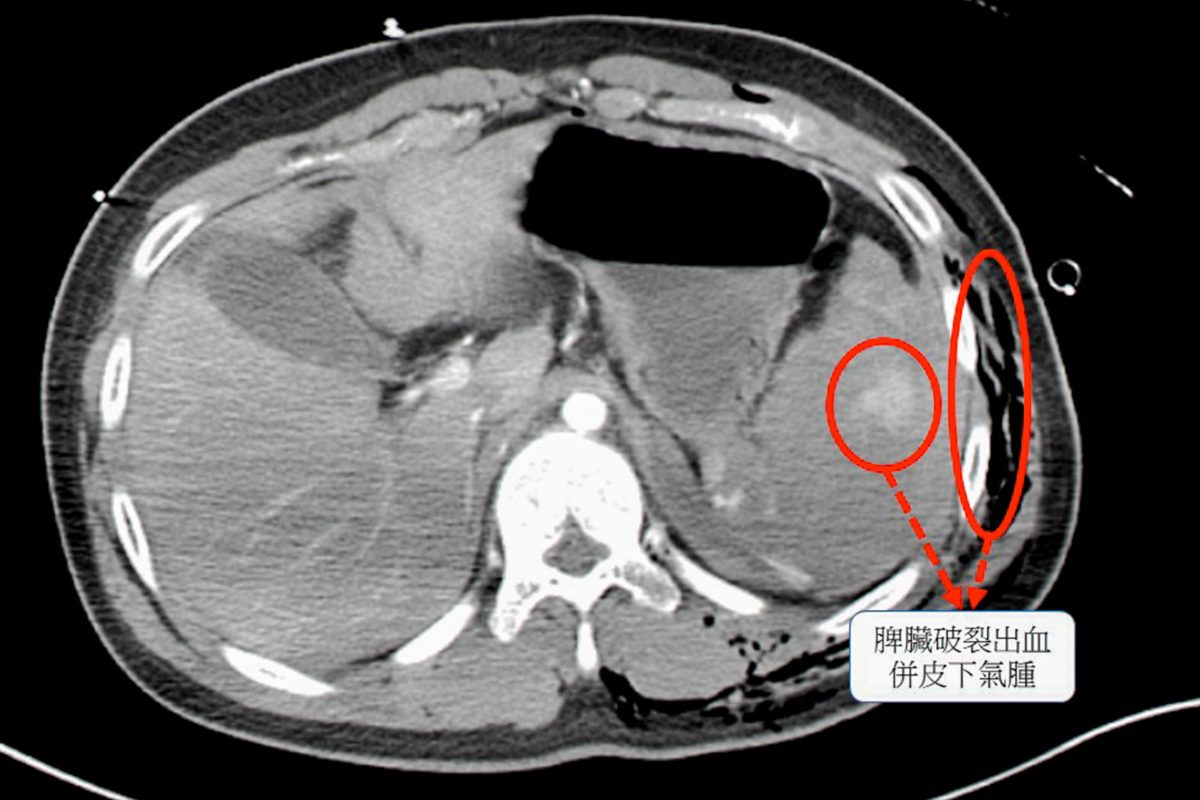

▲經過電腦斷層檢查,確認患者的脾臟已完全碎裂,是體內大出血的主因 ,同時合併胸腔積血、積氣,以及多處骨折與血管撕裂傷 。(圖/彰基提供)

經過電腦斷層檢查,確認患者的脾臟已完全碎裂,是體內大出血的主因 ,同時合併胸腔積血、積氣,以及多處骨折與血管撕裂傷 。面對如此複雜的傷勢,外科團隊首先進行緊急手術,切除破裂的脾臟以控制出血 ,經骨科與整形外科團隊則接力進行骨折固定與血管修補,成功穩定了患者的生命跡象 。